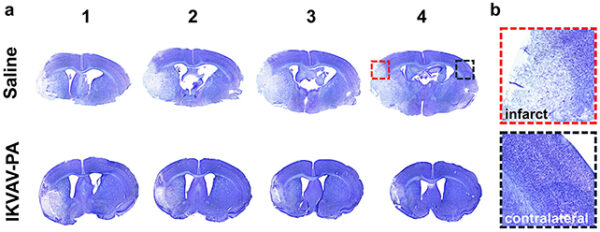

Kết quả thử nghiệm cho thấy, sau khi được tiêm IKVAV-PA và tái lập lưu thông máu não, những con chuột điều trị có mức độ tổn thương mô não thấp hơn rõ rệt, ít viêm hơn và giảm đáng kể các phản ứng miễn dịch có hại so với nhóm không được điều trị. Các tác dụng phụ toàn thân cũng ở mức tối thiểu, cho thấy liệu pháp đã tác động khá chính xác vào vùng não bị đột quỵ.

| Não bộ của những con chuột được điều trị (hàng dưới) cho thấy ít dấu hiệu tổn thương mô não hơn (các vùng có màu nhạt hơn). |

Vai trò chính của IKVAV-PA là kích thích các tế bào thần kinh tự sửa chữa, đồng thời kiểm soát phản ứng viêm ở mức tối thiểu bởi đây là yếu tố có thể làm trầm trọng thêm tổn thương sau khi dòng máu được khôi phục.